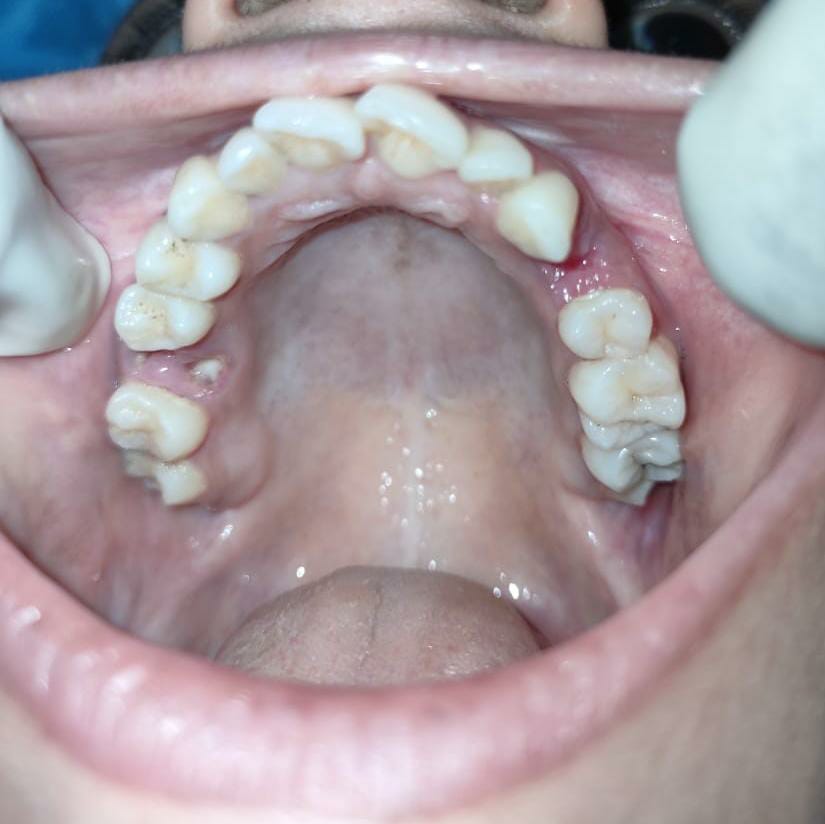

2.4 Live Surgical Demo Of Implant Placement

2.5 Implant Placement

2.6 Implant Placement

2.7 Implant Placement

2.8 Implant Placement

2.9 Implant Placement